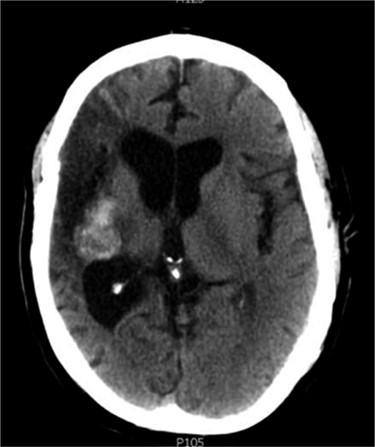

At follow-up it was noted that the patient was experiencing headaches, had poor short-term memory and decreased sensation to the left side of his body. The hemiparesis persisted and a left upper motor neuron facial palsy was noted. In 2005 and in light of persisting symptoms, a follow-up CT scan was reported to show a small, hyper-dense cystic abnormality in the right external capsule (Fig. 1). It was postulated that the lesion was probably a calcified encysted haematoma, and the symptoms were attributed to post-stroke pain.

Axial CT head (2005) demonstrating hyper-dense cystic abnormality in the right external capsule.